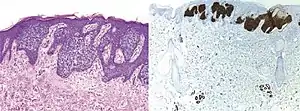

Comparison H&E stain (left) with BerEP4 immunohistochemistry staining (right) on a pathological section having BCC with squamous cell metaplasia. Only BCC cells are stained with BerEP4.[1]

BerEp4 (also Ber-EP4) is a histologic stain mainly used to aid in the diagnosis of basal cell carcinoma (BCC).[2] It is an antibody to EpCAM (epithelial cell adhesion molecule).[1]

BerEp4 has a high sensitivity and specificity in being positive only in BCC cells.[1] BerEp4 is normally negative in squamous epithelium and mesothelium, but otherwise normally positive most epithelial cells of the body.[3] It can also help in distinguishing pulmonary adenocarcinoma (positive BerEp4) from mesothelioma (generally negative BerEp4).[3][4]